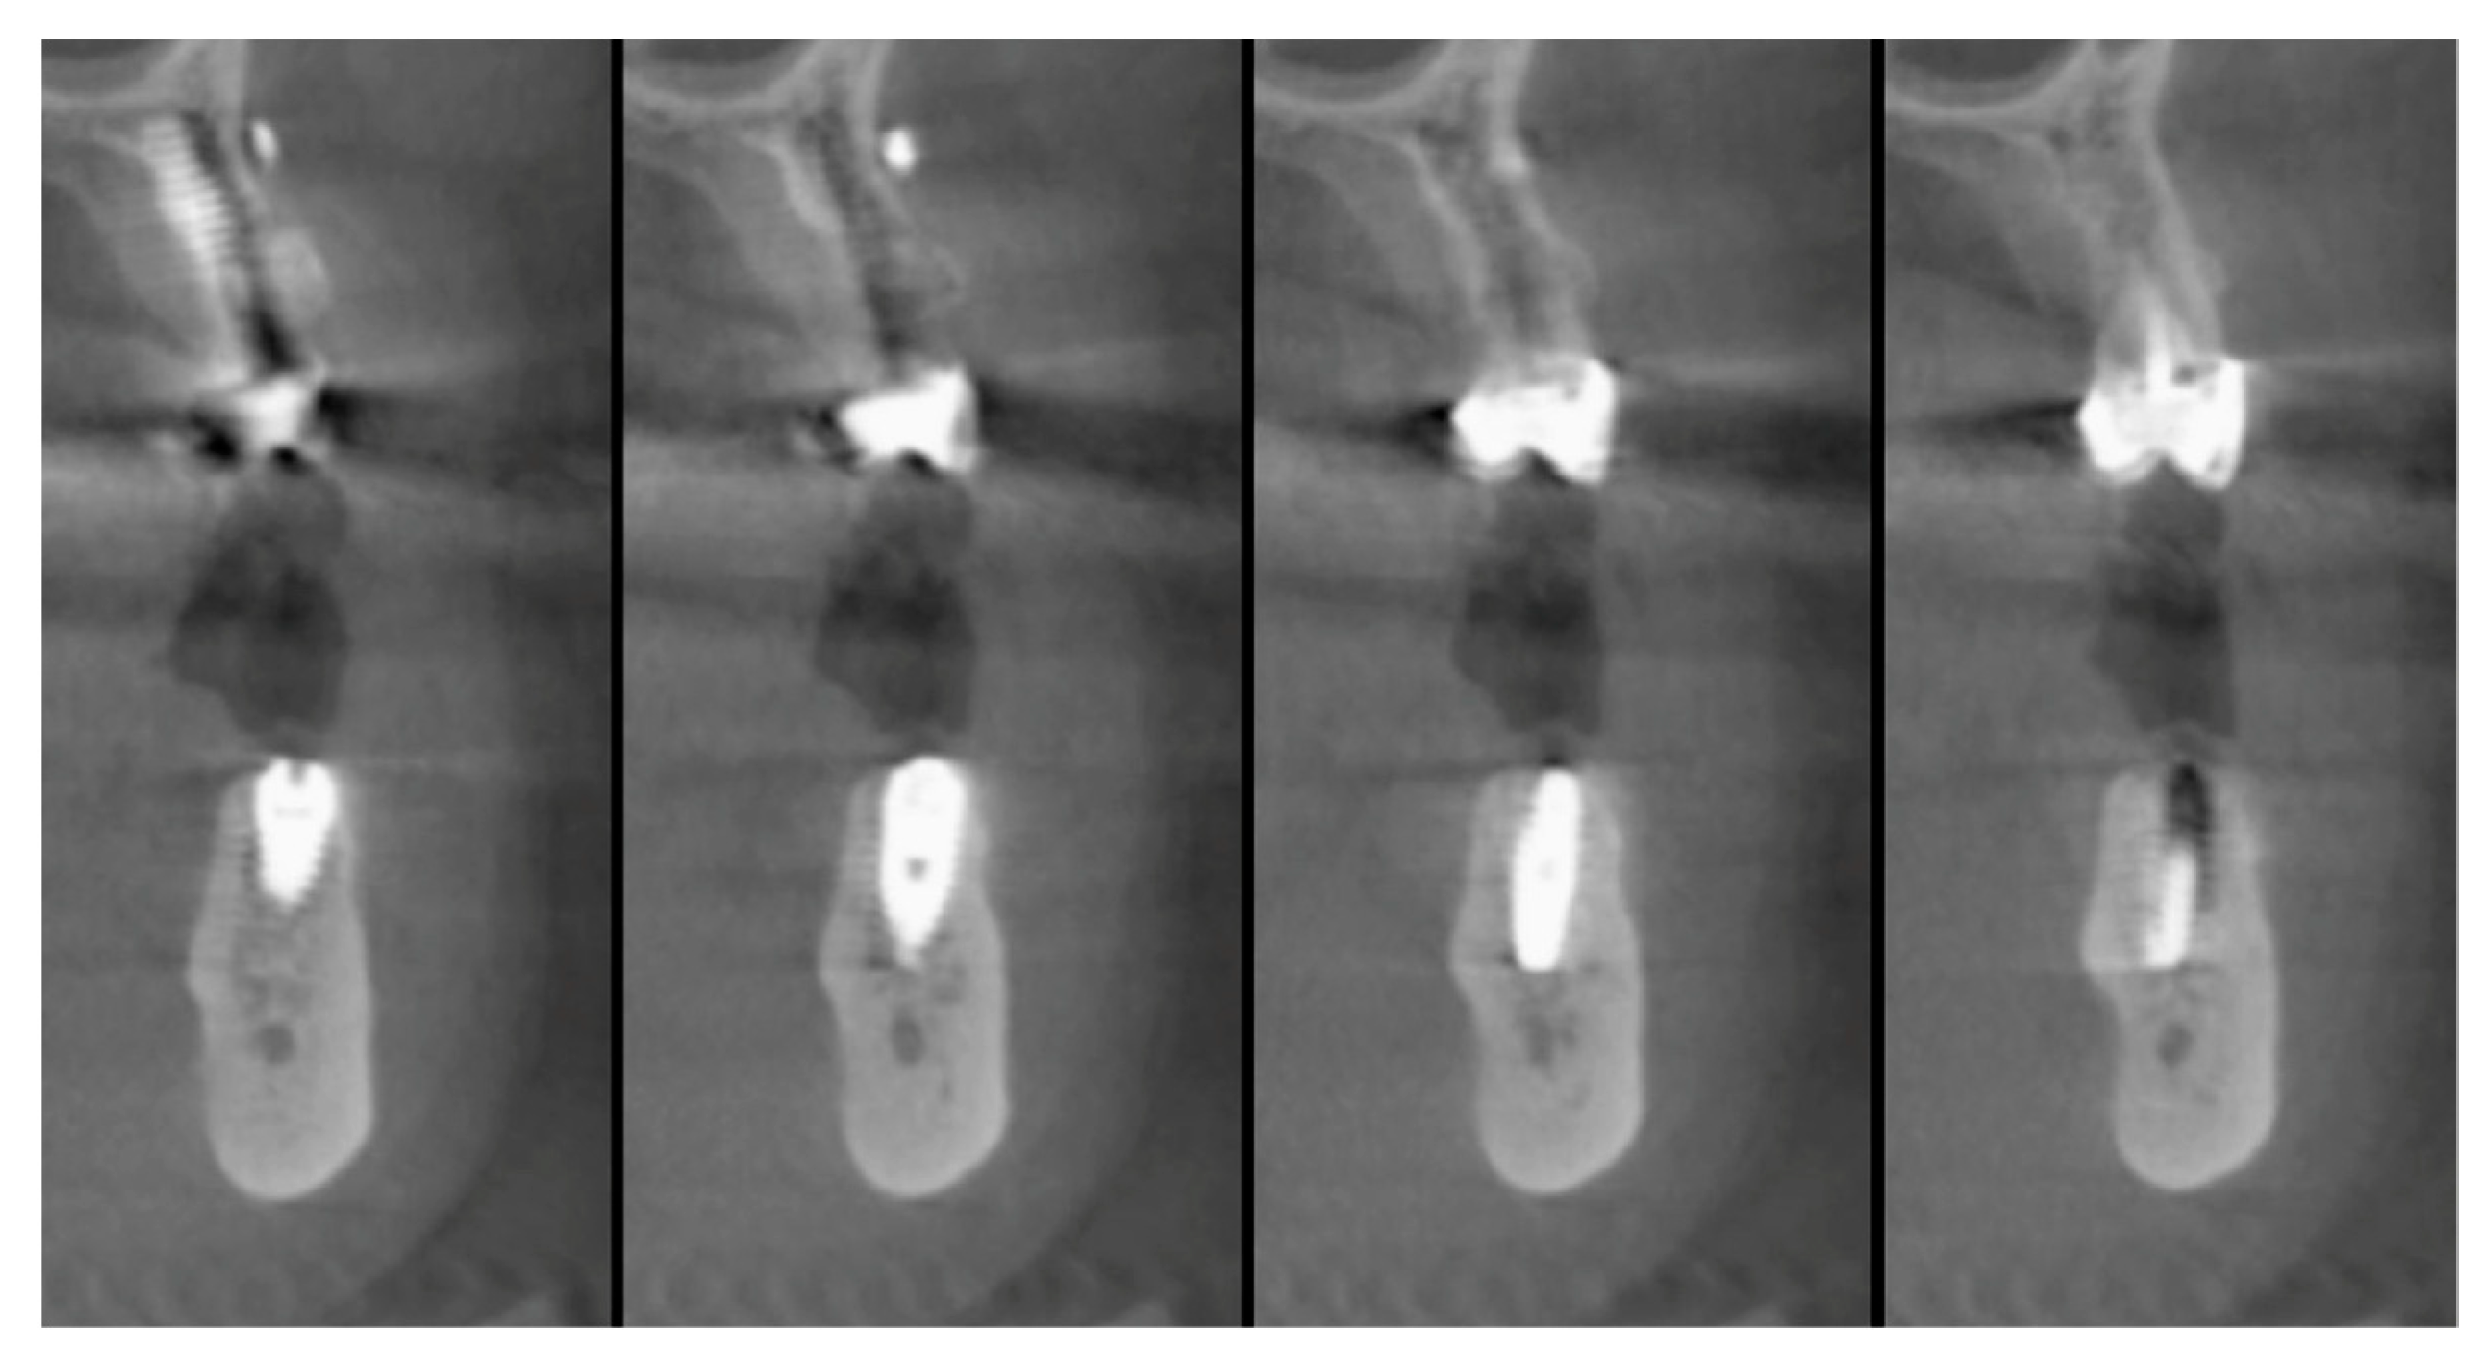

The vertical average defect was 9.16 mm, buccal lateral/palatal 7.0 mm, and mesio-distal 10.3 mm. The measurements were intraoperatively performed with a millimeter periodontal probe. The endodontic material mechanically cleaned before the tooth was placed inside the Tooth Transformer device. The endodontic material was removed using a drill bur with the attention to cut the canal in excess with the aim to remove all the cement. No surgical complications were registered. Pre and post-operative X-rays (section from CBCT) were collected from the same case (Figure 1, Figure 2, Figure 3 and Figure 4). After four months, 13 histological and histomorphometrical evaluations were performed (Figure 5). The Bone Volume/Total Volume average (BV%) was 41.47 (S.D. ± 11.51), the Residual Graft/Total Volume average (Graft%) was 16.60 (S.D. ± 7.09), and the Vital Bone/Total Bone average (VB%) was 21.89 (S.D. ± 9.72). No extraneous material (gutta-percha or cement) was detected in all samples (Table 3).

Figure 2. In the cbct section in zone 36, it is possible to note the bone loss dimension.

Applsci 09 05396 g002

Figure 3. The cbct section in zone 36, two months after the Guided Bone Regeneration (GBR). The defect was completely filled using the endodontical treated elements site 3.5 and 3.6 (Italian teeth numeration).

Applsci 09 05396 g003

Figure 4. The cbct section in zone 36 after the implants healing, six months after the GBR.